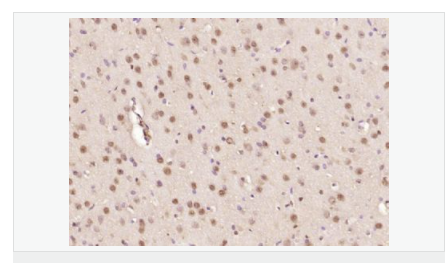

| 产品应用 | ELISA=1:5000-10000 IHC-P=1:100-500 IHC-F=1:100-500 ICC=1:100-500 IF=1:100-500 (石蜡切片需做抗原修复) not yet tested in other applications. optimal dilutions/concentrations should be determined by the end user. |

| 细胞定位 | 细胞核 细胞浆 |

| 产品介绍 | The human ataxin-7 gene, also known as spinocerebellar ataxia 7 or SCA7, maps to chromosome 3p13-p12, has a 2,727-bp open reading frame, and encodes a 892 amino acid protein containing a nuclear localization signal and a polyglutamine tract (1,2). SCA7 is an autosomal dominant neurodegenerative disorder characterized by ataxia and selective neuronal cell loss caused by the expansion of a translated CAG repeat encoding a polyglutamine tract in ataxin-7, which is the SCA7 gene product (3,4). Ataxin-7 is expressed within neurons both affected and unaffected in SCA7 pathology with subcellular localization being variable depending upon the neuronal subtype (5). Polyglutamine expanded in ataxin-7 may carry out its pathogenic effects in the nucleus by altering the matrix-associated nuclear structure and/or by disrupting nucleolar function (6). Function: Ataxin 7 is a protein of unknown function. It may be the human orthologue of the yeast SAGA SGF73 subunit and a subunit of the human TFTC-like transcriptional complexes. Spinocerebellar ataxia 7 (one of a group of hereditary neurodegenrative diseases) is caused by an expanded trinucleotide repeat in the gene encoding ataxin 7. Ataxin 7 is typically located in the cytoplasm and on the nuclear membrane of normal brain neurons. In cells where there is a mutation of the SCA7 gene, ataxin 7 accumulates in intranuclear inclusions and can result in cell death. Subunit: Component of the STAGA transcription coactivator-HAT complex, at least composed of SUPT3H, GCN5L2, TAF5L, TAF6L, SUPT7L, TADA3L, TAD1L, TAF10, TAF12, TRRAP, TAF9 and ATXN7. The STAGA core complex is associated with a subcomplex required for histone deubiquitination composed of ATXN7L3, ENY2 and USP22. Interacts with SORBS1, PSMC1 and CRX. Interacts with TRRAP, GCN5L2 and TAF10. Interacts with alpha tubulin. Subcellular Location: Cytoplasmic (isoform b) and Nuclear (isoform a) Tissue Specificity: Isoform a and isoform b are expressed in CNS, but isoform a is expressed predominantly in the peripherical tissues. Isoform b is also highly expressed in the frontal lobe, skeletal muscle and spinal cord and is expressed at a lower level in the lung, lymphoblast and intestine. Post-translational modifications: Proteolytically cleaved. The cleavage may be involved in SCA7 degeneration: the isoform fragments may exert distinct toxic influences that could contribute to selective neurodegeneration. Sumoylation decreases the aggregation propensity and cellular toxicity of forms with an expanded poly-Gln region but has no effect on subcellular location or interaction with components of the STAGA complex. DISEASE: Defects in ATXN7 are the cause of spinocerebellar ataxia type 7 (SCA7) [MIM:164500]; also known as olivopontocerebellar atrophy III (OPCA III or OPCA3) or olivopontocerebellar atrophy with retinal degeneration. Spinocerebellar ataxia is a clinically and genetically heterogeneous group of cerebellar disorders. Patients show progressive incoordination of gait and often poor coordination of hands, speech and eye movements, due to degeneration of the cerebellum with variable involvement of the brainstem and spinal cord. SCA7 belongs to the autosomal dominant cerebellar ataxias type II (ADCA II) which are characterized by cerebellar ataxia with retinal degeneration and pigmentary macular dystrophy. Similarity: Belongs to the ataxin-7 family. Contains 1 SCA7 domain. SWISS: O15265 Gene ID: 6314 Database links: Entrez Gene: 6314 Human Entrez Gene: 246103 Mouse Omim: 164500 Human Omim: 607640 Human SwissProt: O15265 Human SwissProt: Q8R4I1 Mouse Unigene: 476595 Human Important Note: This product as supplied is intended for research use only, not for use in human, therapeutic or diagnostic applications. |